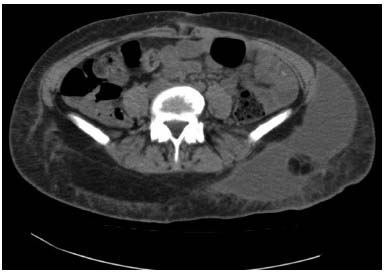

Seroma is a fluid collection occurring postoperatively in the body-contouring patient in a surgically created dead space resulting from skin removal. Seromas may be difficult to distinguish from lymphoceles. Extensive undermining, shear forces, lymphatic disruption, and possible secondary surgery, combined with underlying malnutrition with low albumin levels, make this complication one that is frequently experienced. This is the most common complication after lower body lift, with contemporary reports of clinically evident seromas reported in 8 to 37.5% of cases,14 18%,11 20.9%,10 8%,15 and 37.5%.12,13 When they occur with circumferential torsoplasty, many seromas are posterolaterally located ( Fig. 16.3 ).10,12,13 Location in the flank and thigh is probably secondary to motion of the greater trochanter with ambulation and dependency. Pascal and Le Louarn16 place quilting sutures in this location, which may account for their reported very low seroma rate.